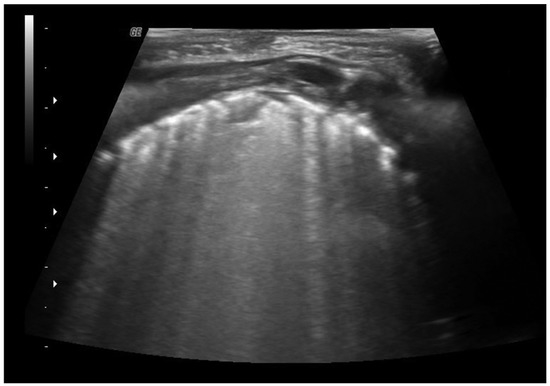

4.5. Pulmonary Edema

4.6. Pleural Pathologies and Complications of Pneumonia